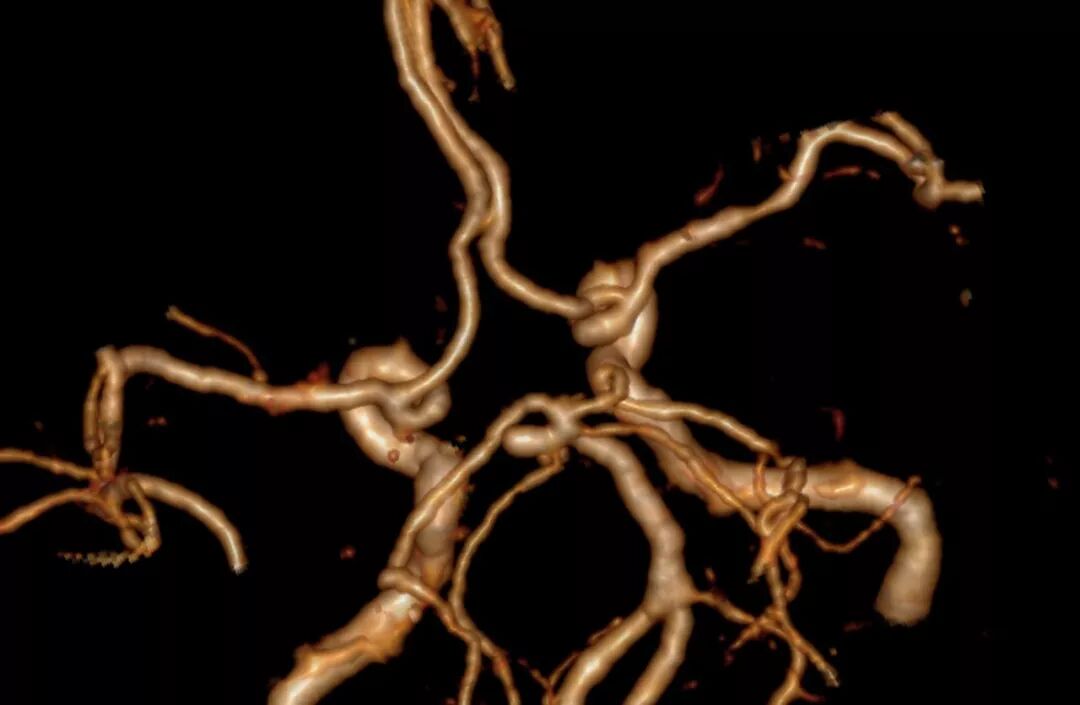

术前外院DSA提示:左侧颈内动脉后交通动脉瘤呈不规则腊肠形,约4*10mm,右侧小脑上动脉瘤呈球形,约3*4mm,胼周动脉瘤,约2*3mm。

图1-1. 外院头颅DSA结果提示颅内多发动脉瘤:分别为左侧颈内后交通动脉瘤、右侧小脑上动脉瘤、胼周动脉瘤。